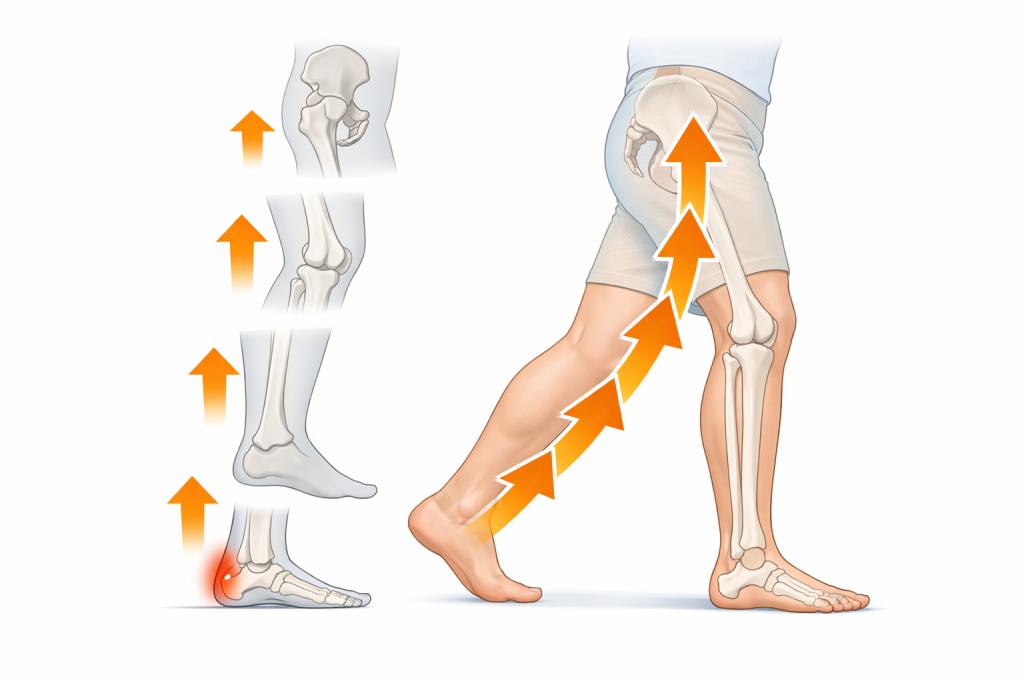

本来、歩行時の衝撃は

足首 → ふくらはぎ → 膝 → 股関節

へと分散されます。

この連動が崩れることで、

最後の受け皿として足底筋膜に負担が集中します。